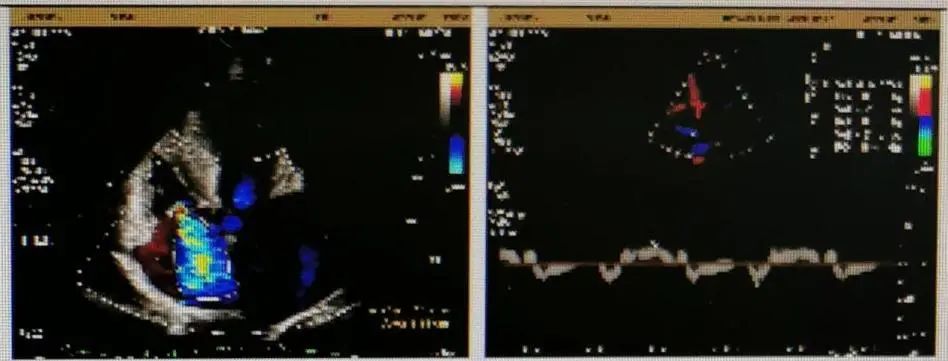

超声检查

超声结果显示主动脉瓣退行性病变,重度狭窄并轻度反流;主动脉瓣瓣口流速5.9m/s,峰值跨瓣压差138mmHg,平均跨瓣压差72mmHg,瓣环内径20mm,升主增宽,主动脉弓内径36mm,反流彩束面积2.3cm²,LVOT-VTI:28.9cm。此外,患者同时合并左室壁增厚,左室舒张功能减退,节段性室壁运动异常,重度二尖瓣反流,重度三尖瓣返流,轻度肺高压。